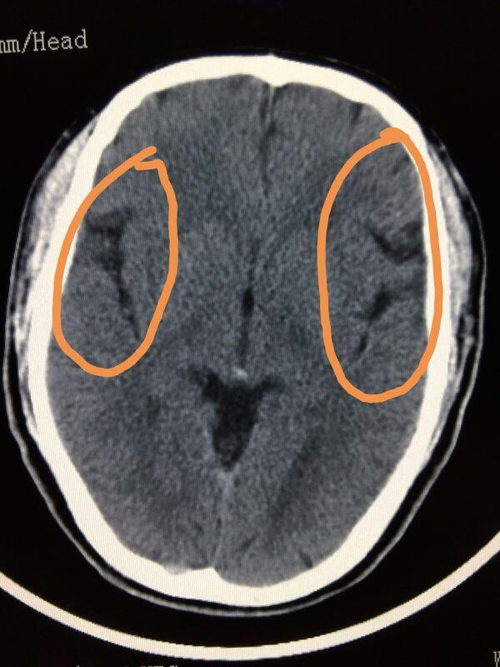

酒精中毒致使脑沟消失(一位医生的微信截图)。

在医院ICU(重症监护室)的办公室,记者见到了当时的接诊医生县第一医院重症监护室主治医生王平。他告诉记者,病人是在1月4日晚10点左右醉酒回家,次日早上7点多被家人送进急诊。这位小伙子被送进医院时已经深度昏迷,双侧瞳孔出现不等大情况,舌根后坠,肺内有渗出性病变,考虑出现了误吸,同时脑CT显示他的脑沟消失,提示酒精中毒的急性作用,伴脑实质缺氧。王平介绍说,酒精中毒,也就是我们常说的醉酒,不少人会出现气道保护能力下降的情况,因此在呕吐的时候,容易导致胃内容物逆流进入咽喉腔及气管内,造成这种误吸情况。

因小伙子酒精中毒程度深,医院立即对其进行了会诊,并在进行保护性气管插管后,直接转入ICU进行治疗和观察。经抢救,小伙子逐渐恢复清醒,目前已经出院。王平说,酒精中毒致使脑沟消失的病人他也是第一次遇见,主要原因是脑水肿造成,家人如果没有及时发现并送医,这位年仅26岁的小伙子极有可能会有生命危险。